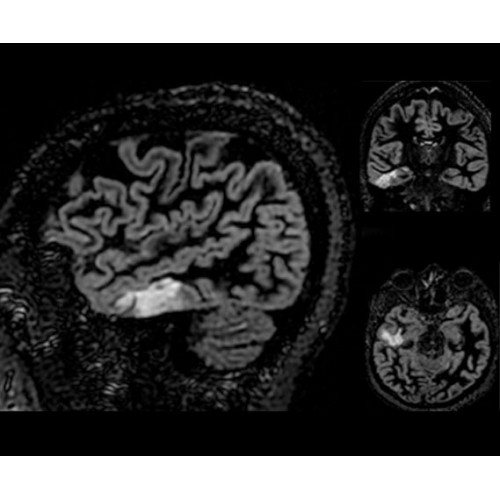

Теперь возможности МРТ поражают еще больше благодаря ультрасовременным решениям для визуализации с SIGNA Architect 3.0 Тл, объединяющей новейшие достижения в области МР-технологий и интуитивно понятный интерфейс. Система SIGNA Architect, разработанная на базе новой платформы SIGNA Works, представляет собой гармоничное сочетание дизайна и функциональности. Каждый элемент системы направлен на повышение производительности, эффективности клинической практики, финансовых показателей, а также комфорта и безопасности пациента.

Поле обзора 50x50x50 см и апертура шириной 70 см позволят достоверно визуализировать сложные анатомические области для пациентов с крупным телосложением, например, плечи и бедра. Феноменальная однородность системы SIGNA Architect обеспечивает наиболее широкое поле обзора с улучшенными характеристиками градиентов. Ничто не останется незамеченным.

• NeuroWorks — универсальное решение для визуализации анатомии головного мозга, позвоночника, сосудов и периферических нервов с четкой дифференциацией тканей.